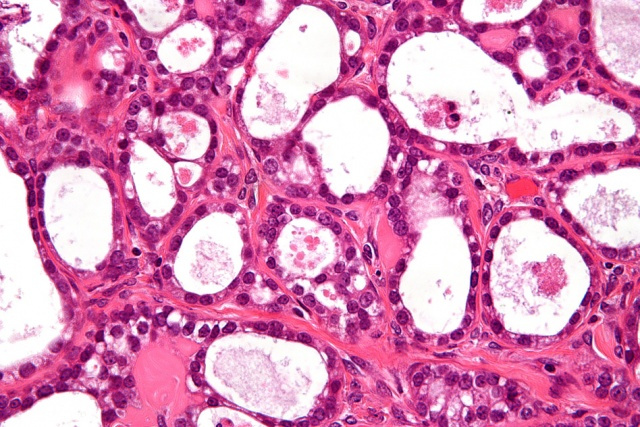

A high-magnification micrograph of an ovarian clear cell carcinoma. The images show, focally, the characteristic clear cells with prominent nucleoli and the typical hyaline globules. A high-magnification micrograph of an ovarian clear cell carcinoma. The images show, focally, the characteristic clear cells with prominent nucleoli and the typical hyaline globules.